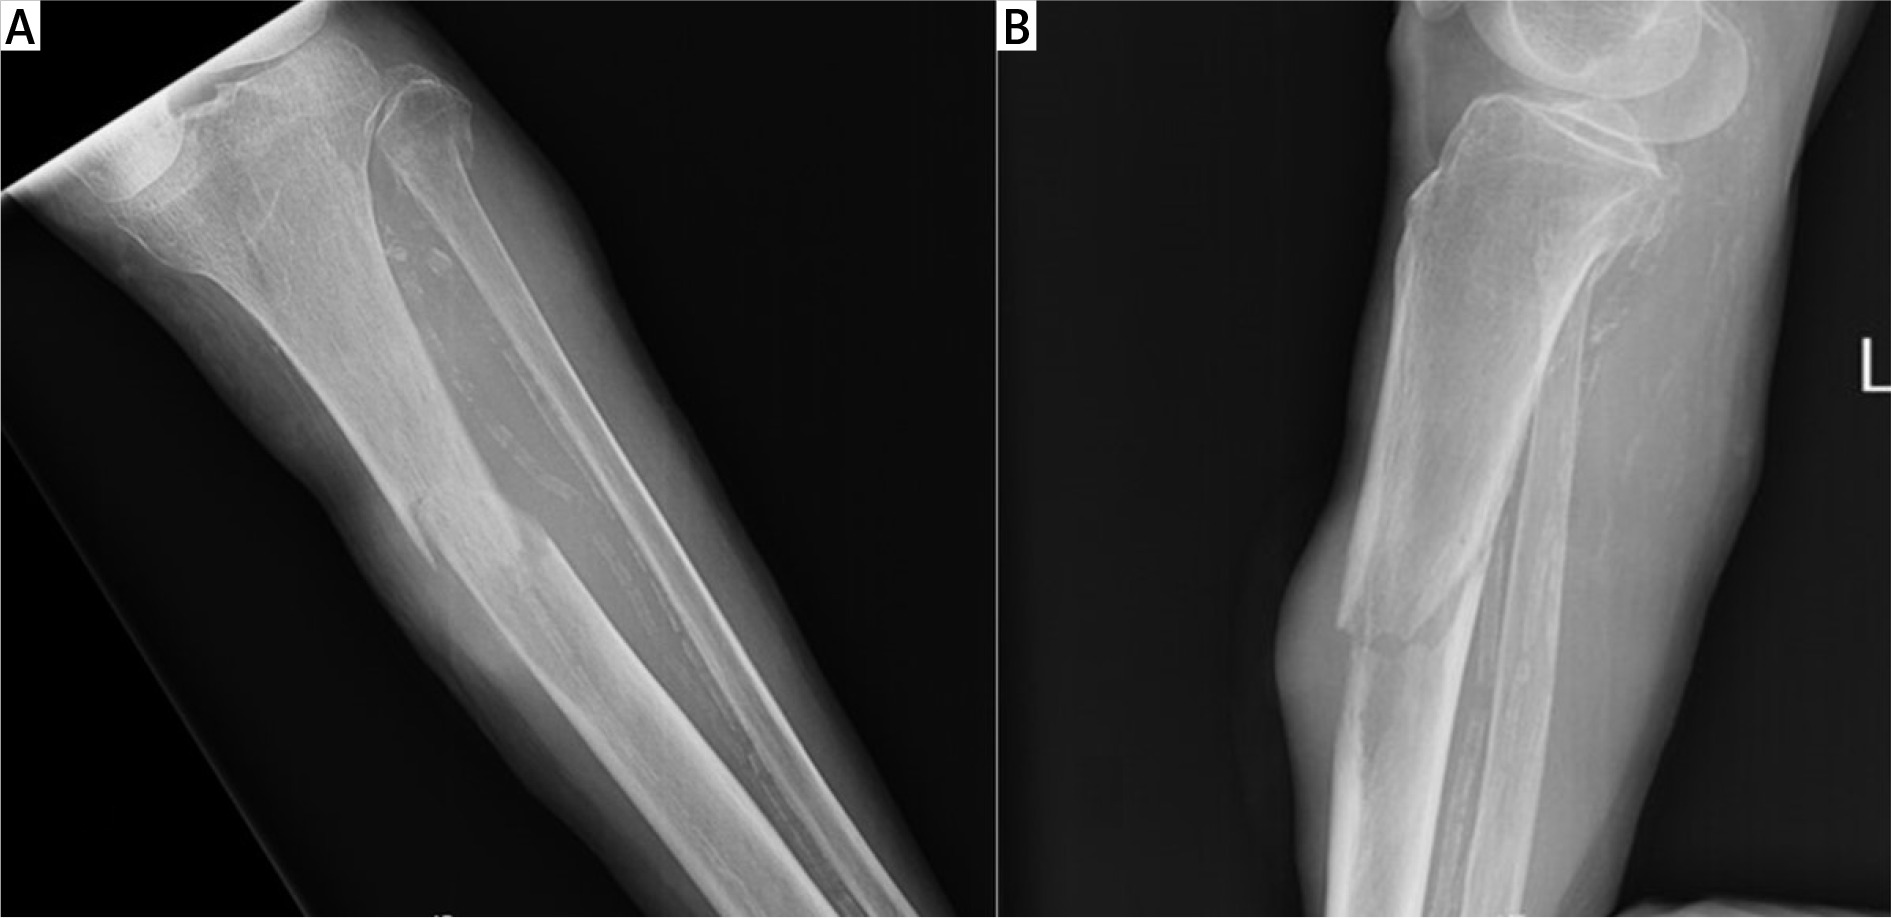

We report a case of a 78-year-old female patient with medical history of hypertension and benign tumour of the uterus for which she had undergone hysterectomy 12 years earlier. She presented at our emergency department due to an atraumatic pretibial swelling of the left leg that she noticed 1 month earlier. Plain radiography did not detect any pathology, although decreased soft tissue transparency around the proximal tibia was seen (Figure 1). Under local anaesthesia the swelling was incised and a serous-bloody collection evacuated. During the procedure the tibial bone surface was found to be irregular, but no further investigations were made, and the patient was discharged. The wound dressing was changed every 2 days in the outpatient service. Swab culture from the incised place was sterile.

Figure 1

Plain radiography reveals altered bone structure of the proximal tibial diaphysis as well as decreased surrounding soft tissue transparency

On the 17th postoperative day, during a regular walk, the patient fell and broke a leg. She was brought to our emergency department, where a pathologic fracture of the proximal tibial diaphysis was diagnosed on X-ray, just at the level of the prior incision (Figures 2 A, B). Laboratory analysis showed signs of anaemia with a slightly decreased haemoglobin level (108 g/l; NL 119–157 g/l) and decreased erythrocytes (3.81 × 106/ml; NL 3.86–5.08 × 106/ml). The CA-125 tumour marker was elevated (36.3 kIU/l; NL < 35 kIU/l), and AFP was also slightly increased (11.5 µg/l; NL < 9 µg/l).